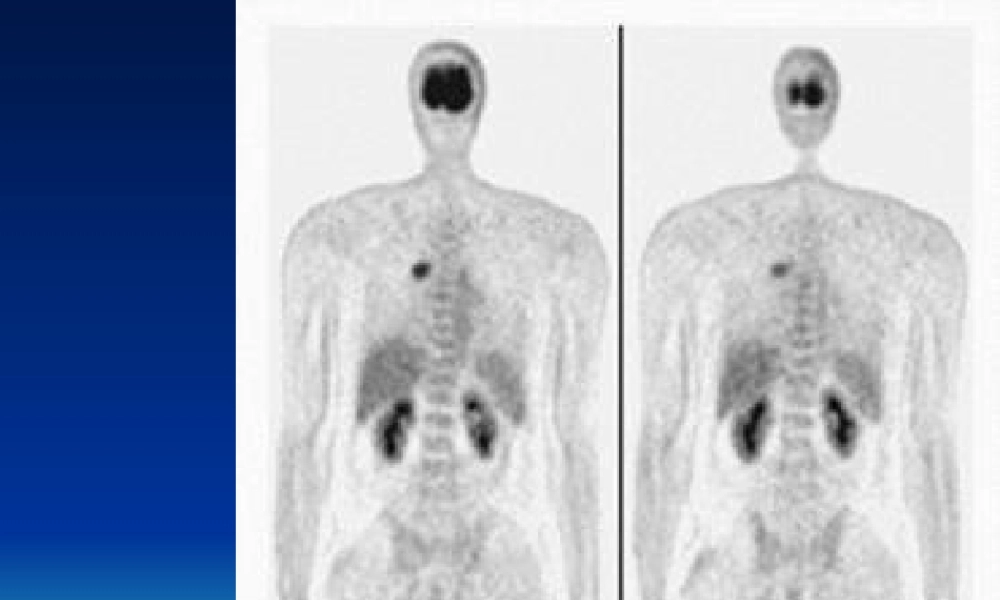

【病史】男,43岁,咳嗽、咳痰半年余,无咯血及体重下降【病史】男,56岁。CT发现颅病例12【病史】男,28岁,头痛、性格改变约半年,MR示右额叶T2信号增高。病例15(fànɡliáo)后1年。病例40【病史】女,58岁。CT查体发现(fāxiàn)胰体尾部占位性病变,大小约10cm。无特殊临床症状。病例43SUV为5.5。病例52【病史(bìnɡshǐ)】男,56岁。腰痛2月,CT、MR示腰4椎体骨质破坏,行手术部分切除,病理为转移性腺癌。胸、腹部及盆腔CT及前列腺B超皆未找到原发灶。(chūxiàn)